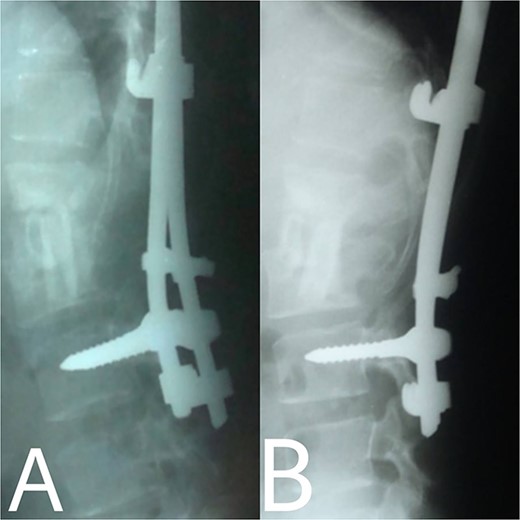

(A, B) Post-operation, anteroposterior and lateral view showing fibular autograft implantation followed by supplemental posterior instrumentation.